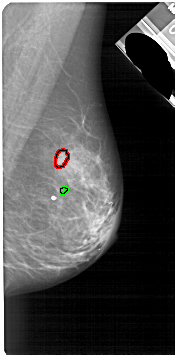

A_1791_1.RIGHT_CC

RIGHT_CC LINES 4591 PIXELS_PER_LINE 2506 BITS_PER_PIXEL 12 RESOLUTION 43.5 OVERLAY

FILE: A_1791_1.RIGHT_CC.OVERLAY

TOTAL_ABNORMALITIES 1

ABNORMALITY 1

LESION_TYPE CALCIFICATION TYPE PLEOMORPHIC DISTRIBUTION CLUSTERED

ASSESSMENT 4

SUBTLETY 2

PATHOLOGY BENIGN

TOTAL_OUTLINES 1

BOUNDARY

ABNORMALITY 2